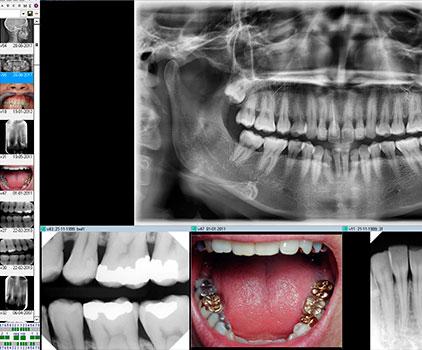

Panoramarøntgen giver et samlet billede af alle tænder i over- og underkæbe og bruges bl.a. til at opdage frakturer, cyster og infektioner samt ved bøjle-, implantat- og protesebehandling.

3D-røntgen viser mundens strukturer fra alle vinkler – inkl. knogler, blødt væv og nerver – og giver et præcist grundlag for behandlinger som implantater og rodbehandlinger.